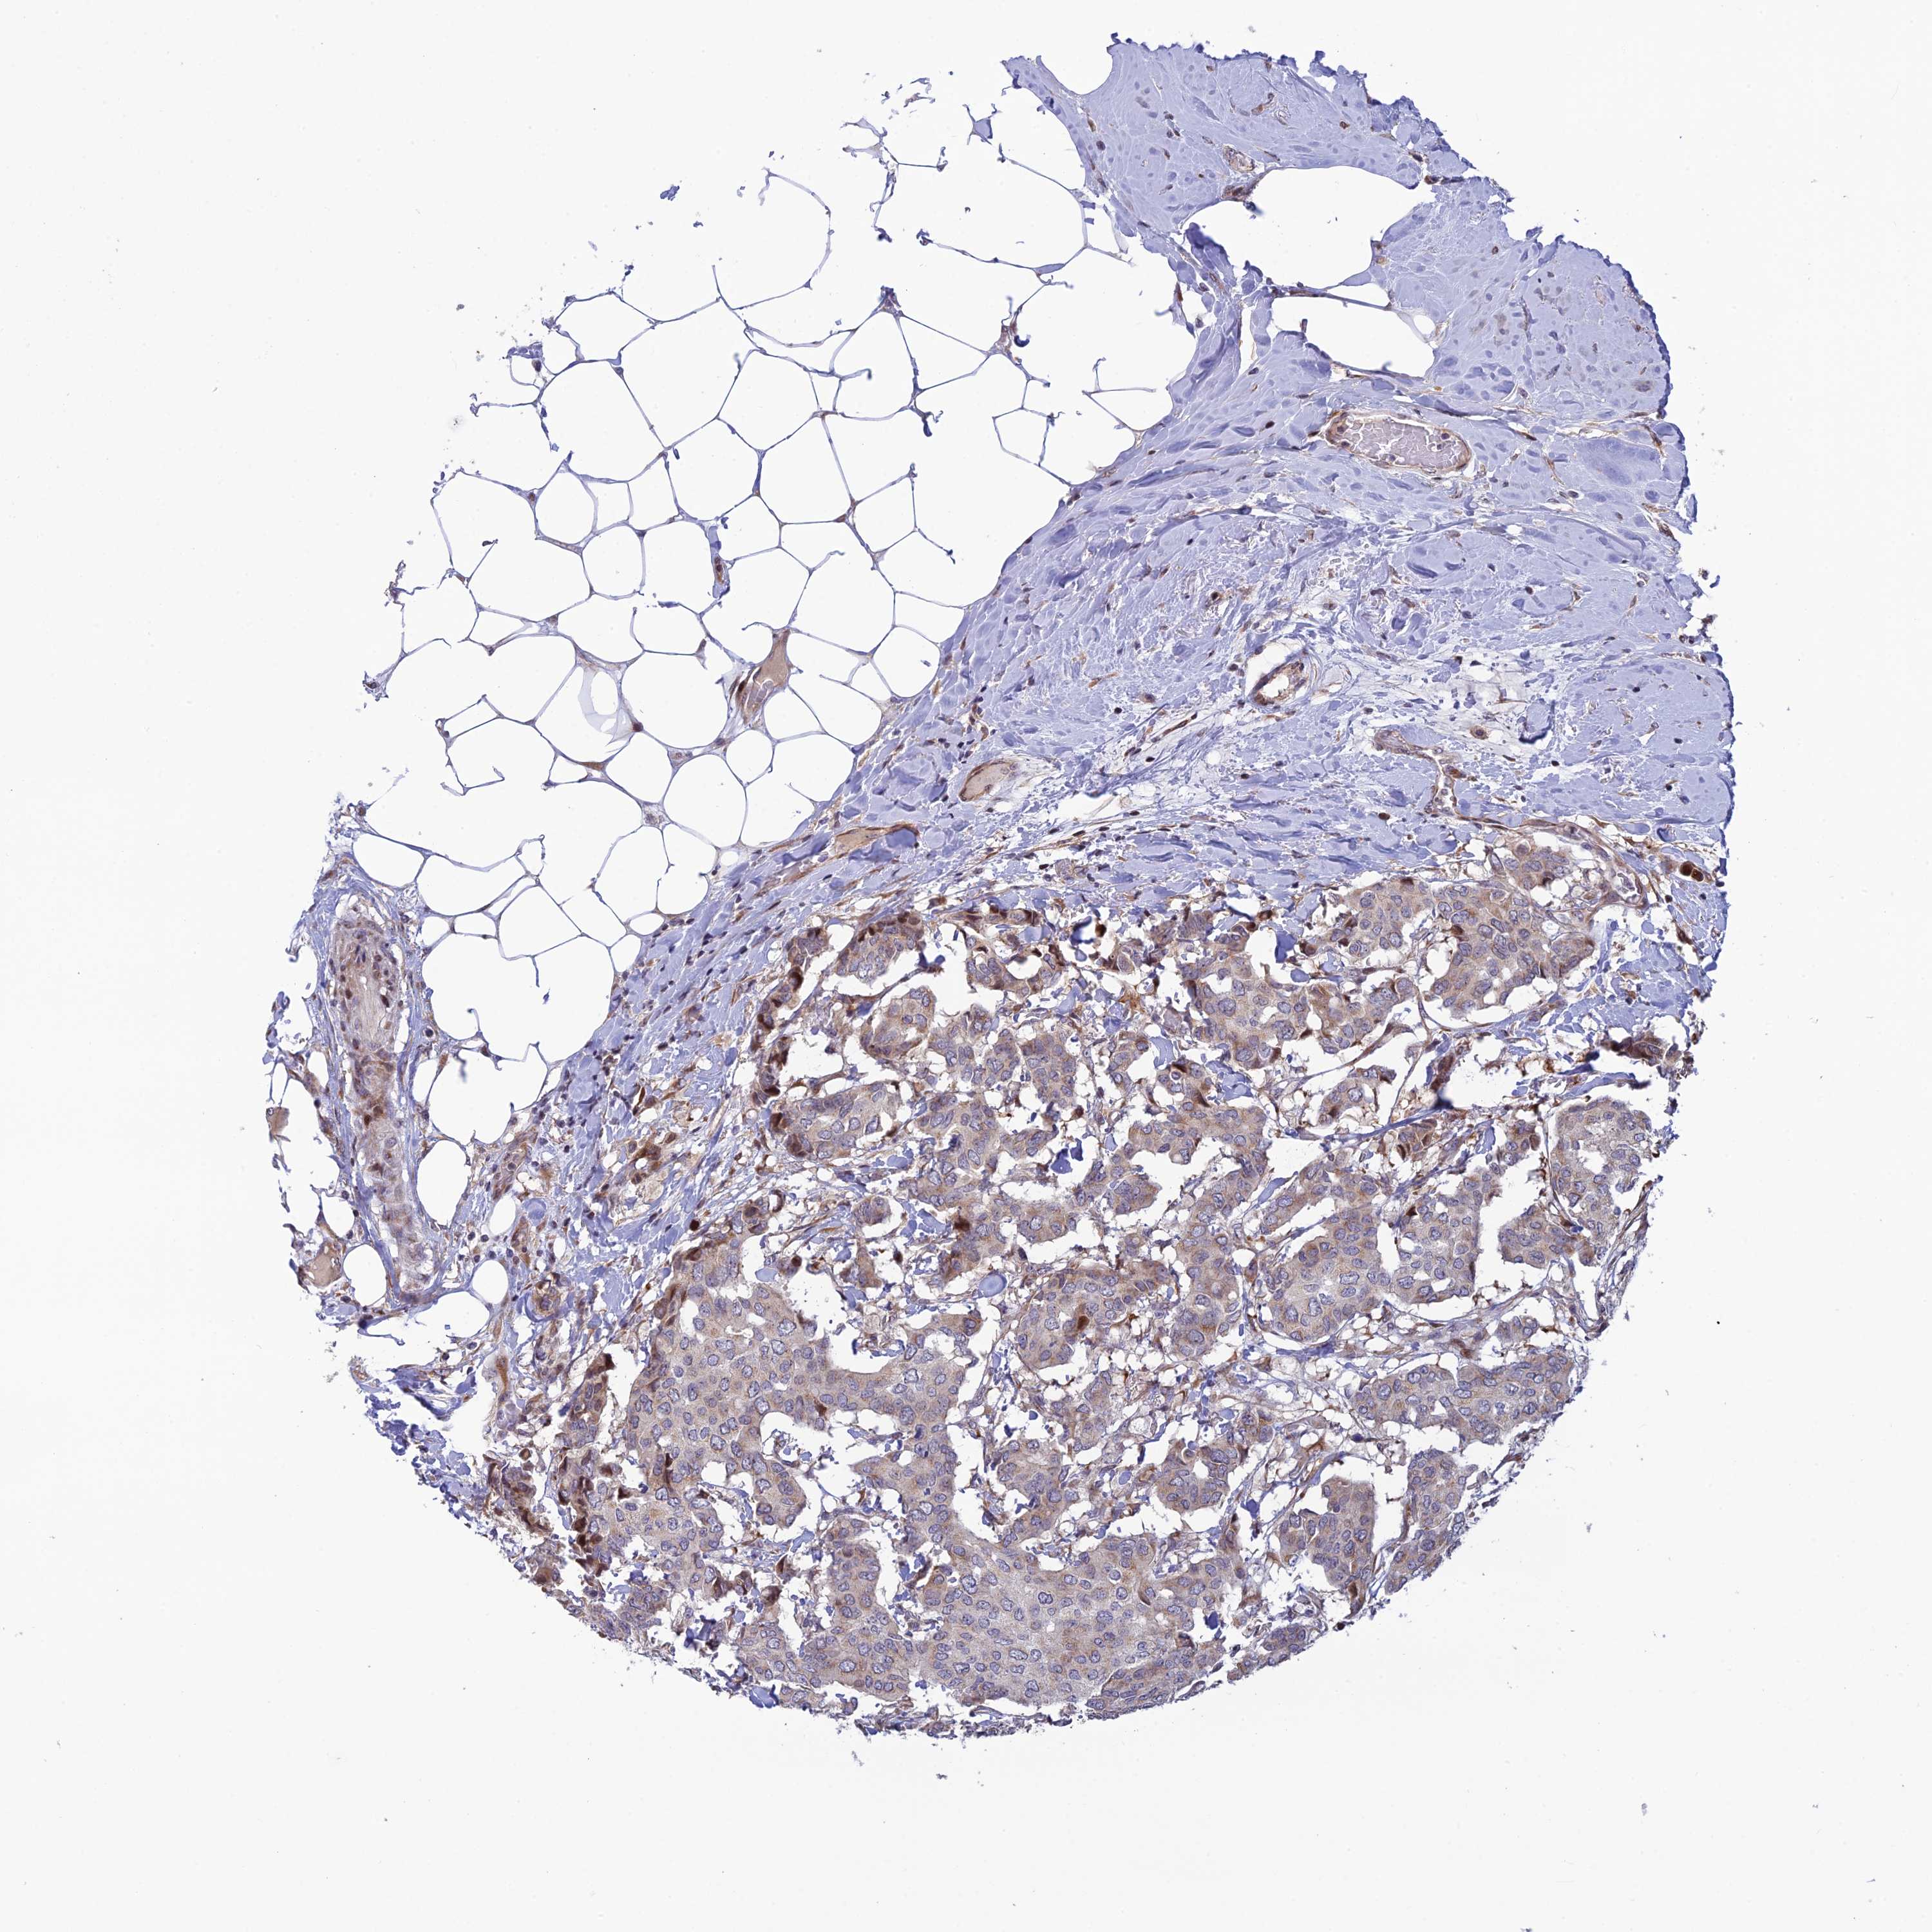

CANCER BREAST CANCER Show tissue menu

BRCA TCGA BRCA VALIDATION PROTEIN EXPRESSION